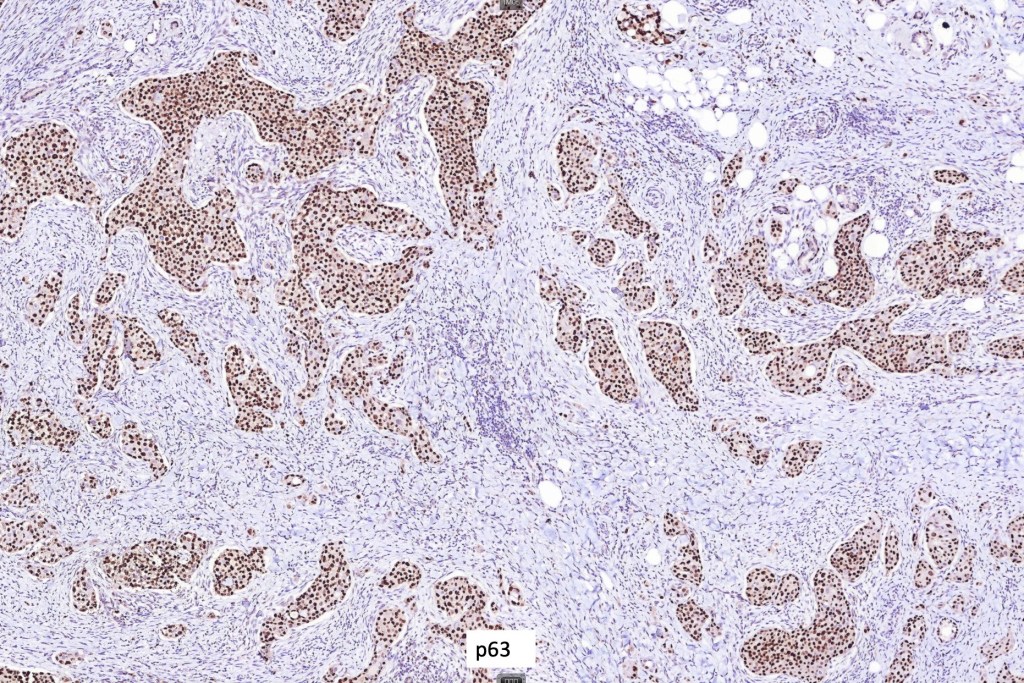

Immunohistochemistry (all images are courtesy of Dr. Kalmykova except for CK7 which was shared by Dr. Phyo)

•CAM 5.2, AE1/AE3, CK5/6, EMA, CEA, GATA3, androgen receptor, GCDFP15 and D2-40 positive

•Variable S100, SMA and p63 expression